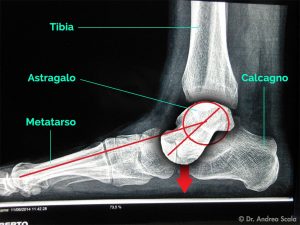

La causa? Sindrome del tunnel tarsale

È causata dalla compressione del nervo tibiale posteriore nel piccolo spazio (tunnel tarsale) che sta al di sotto del malleolo tibiale della caviglia, delimitato da due ossa: il calcagno e l’astragalo. Sotto i legamenti, nel tunnel tarsale scorrono i tendini del tibiale posteriore e del flessore lungo delle dita, l’arteria, la vena e il nervo tibiale posteriore. Uno spazio molto affollato! Nel corridore la sindrome del tunnel tarsale è normalmente determinata dall’infiammazione del tendine del tibiale posteriore (tenosinovite) che comprime il nervo, riducendo lo spazio all’interno del tunnel. Inoltre l’infortunio può essere favorito da una pronazione esagerata, che crea un grande stress sulla parte mediale della caviglia e dall’uso di scarpe inadeguate a correggere gli eccessi dell’appoggio. Il dolore è localizzato sotto il malleolo tibiale e s’irradia con bruciore e parestesie (formicolii) sotto il piede e sino alle dita.